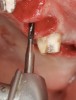

With a 2-mm twist drill in the handpiece, the head of this tool is aimed at the opposite jaw to attain the proper angulation for drilling the osteotomy. The initial development of the osteotomy with the 2-mm drill should be done to a depth of approximately 5 mm, and then a guide pin should be placed to assess osteotomy angulation (Figure 8).29 At this juncture, alterations in angulation can be done with the twist drill. Also, guide pins can be placed into multiple osteotomies to assess parallelism between implants and/or adjacent structures. At this early stage, parallelism should be adjusted as necessary.

When a 2-mm twist drill is used to full depth of the osteotomy (eg, 10 mm), it is difficult to change osteotomy angulation with a twist drill. If a correction is necessary, a side-cutting bur (eg, Lindemann) should be used (Figure 9). Furthermore, if there are doubts as to closeness of the osteotomy to adjacent teeth or vital structures, then a radiograph with a guide pin in place should be obtained.30 Ultimately, the angulation and location of the osteotomy should be consistent with design of the future restoration.31